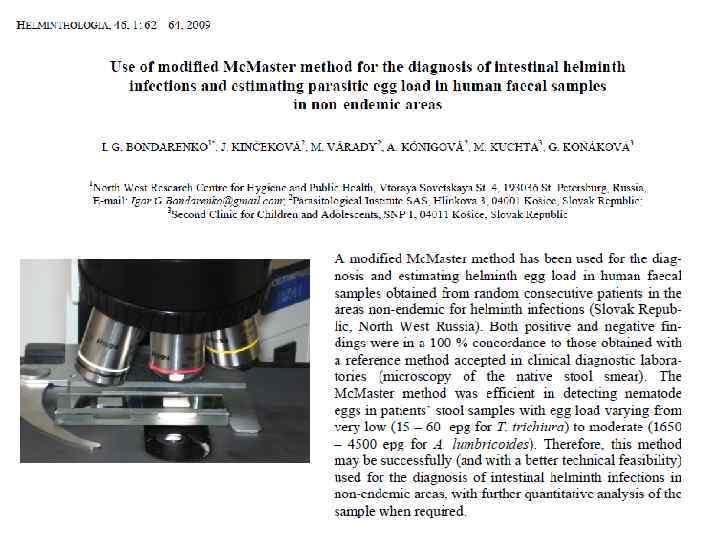

Причины ложноотрицательных результатов исследования «кала на яйца глист» 2. Аналитические причины: а) В лабораториях часто анализируют обычный нативный толстый мазок кала. Методики, предусматривающие обесцвечивание (Kato-Katz) или флотацию (Mc. Master), не используются.